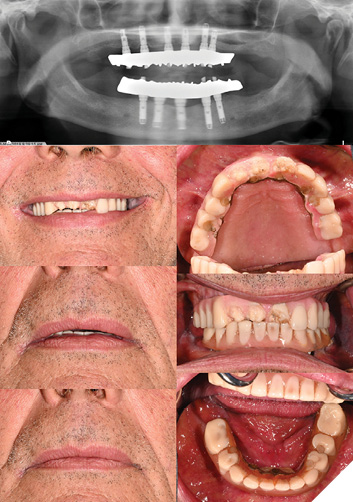

2. Retread: Utilizing existing reference

76y/o male ASA II patient presents seeking repair of fractured teeth #12, 11, 21 on maxillary hybrid IS-FDP

Clinical examination:

- Extraoral examination: Apparent loss of VDO (downturned lips, angular cheilitis, closest speaking space)

- Intraoral examination: Heavily worn teeth with framework visible, history of repeated fractures, no nightguard usage

- Opposing dentition: Mandibular IS-FDP

– Prostheses age: 25 years (framework fabricated in 1999)

- Last retread: 7 years (2017)

- Repaired 4 times since 2020

- Existing master casts with implant analogs and models of prostheses after last retread

– Treatment provided: retread of maxillary and mandibular IS-FDP

Sequence of appointments (Figs. 3-5):

3. Retread: Without existing reference

79-year-old female ASA II patient presents with chief concern of suboptimal esthetics and desire to replace existing maxillary denture and Md IS-FDP. Pt reports history of accidental cheek/gum biting which causes discomfort, and concern that thinning of denture will increase risk of fracture.

Clinical findings:

- Extraoral exam: Apparent loss of VDO, no incisal display at rest or in maximum smile, low lip line, inadequate soft tissue support

- TMJ asymptomatic, click on opening (disc displacement with reduction)

- Patient is dissatisfied with esthetics of smile

– Intraoral exam: Severe residual ridge resorption (RRR) in maxilla with a mobile, flabby ridge

- CUD: poor stability, support, moderate retention

- Heavily worn teeth

- Md IS-FDP has ridge-lap design, pt reports significant food impaction

- General BOP-Dx peri-implant mucositis

Age of prostheses:

- Md IS-FDP 2006 (original veneering material present)

- Mx CD 2019 (origin: Philippines)

Treatment provided: new Mx complete denture, retread of Md hybrid IS-FDP and periodontal therapy to manage peri-implant mucositis

– As there is no available reference prosthesis for the mandibular arch and a new complete denture is planned, the sequence of steps for the Md IS-FDP retread will follow conventional steps in denture fabrication.

Treatment sequence (Figs. 7-12):